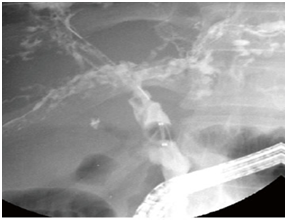

Figure 4 Leimmel syndrome.

Duodenal diverticula (Leimmel Syndrome (Figure 4)